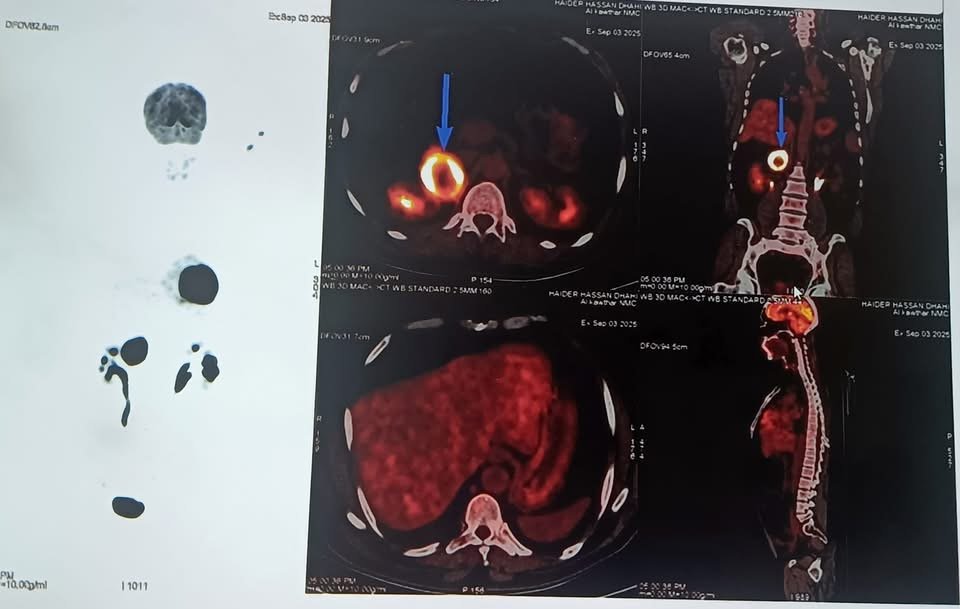

المريض، البالغ من العمر ٤٤ عامًا، راجعَ مركز الفيحاء التخصصي بعد معاناة طويلة من ارتفاع شديد في ضغط الدم وتسارع حاد في ضربات القلب. وبعد إجراء الفحوصات اللازمة، تبيّن وجود ورم كبير في الغدة الكظرية اليمنى، يفرز كميات مرتفعة جدًا من هرمون النور أدرينالين (Pheochromocytoma)، ما شكّل خطرًا كبيرًا على حياته.

وقد استغرق التحضير للعملية شهرين، تضمن برنامجًا علاجيًا دقيقًا باستخدام أدوية خاصة للسيطرة على ضغط الدم ومعدل ضربات القلب، وفق البروتوكولات الطبية المعتمدة، لضمان استقرار حالته قبل العملية.